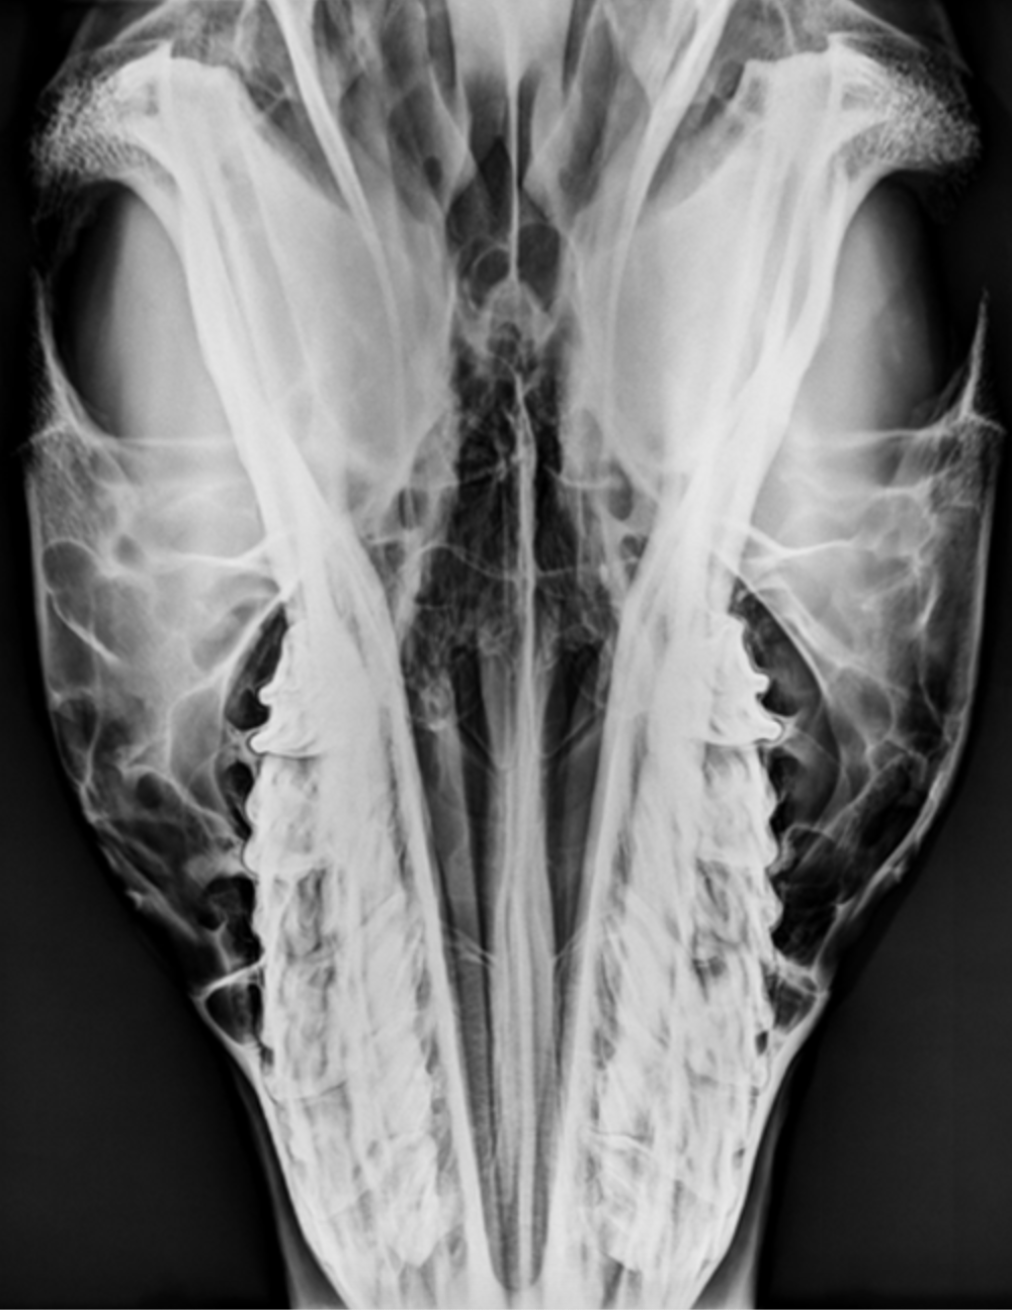

The sinuses have been impregnated with silver to highlight their extent and boundaries. Note the extent of the frontal and maxillary sinuses and their relationship to each other. The boney septum which divides the maxillary sinus into a rostral and caudal compartment is also highlighted. Identify 1-4.

1 =infraorbital canal

2 = frontal sinus

3= septum separating caudal maxillary sinus from rostral compartment

4= rostral maxillary sinus

Which cheek teeth lie within the rostral maxillary sinus and which lie within the caudal maxillary sinus?

¾ and 5/6

The rostral and caudal maxillary sinuses increase in size with age as the reserve crowns of the cheek teeth move down as the teeth wear.